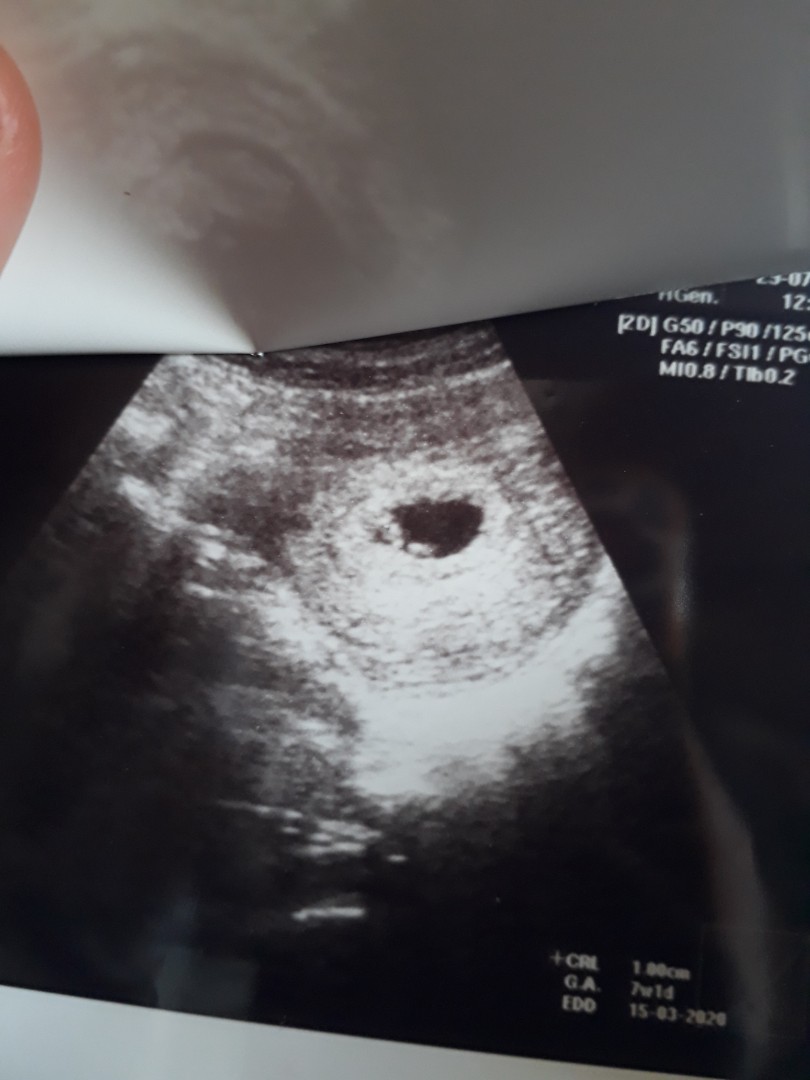

6w2d ค่ะ